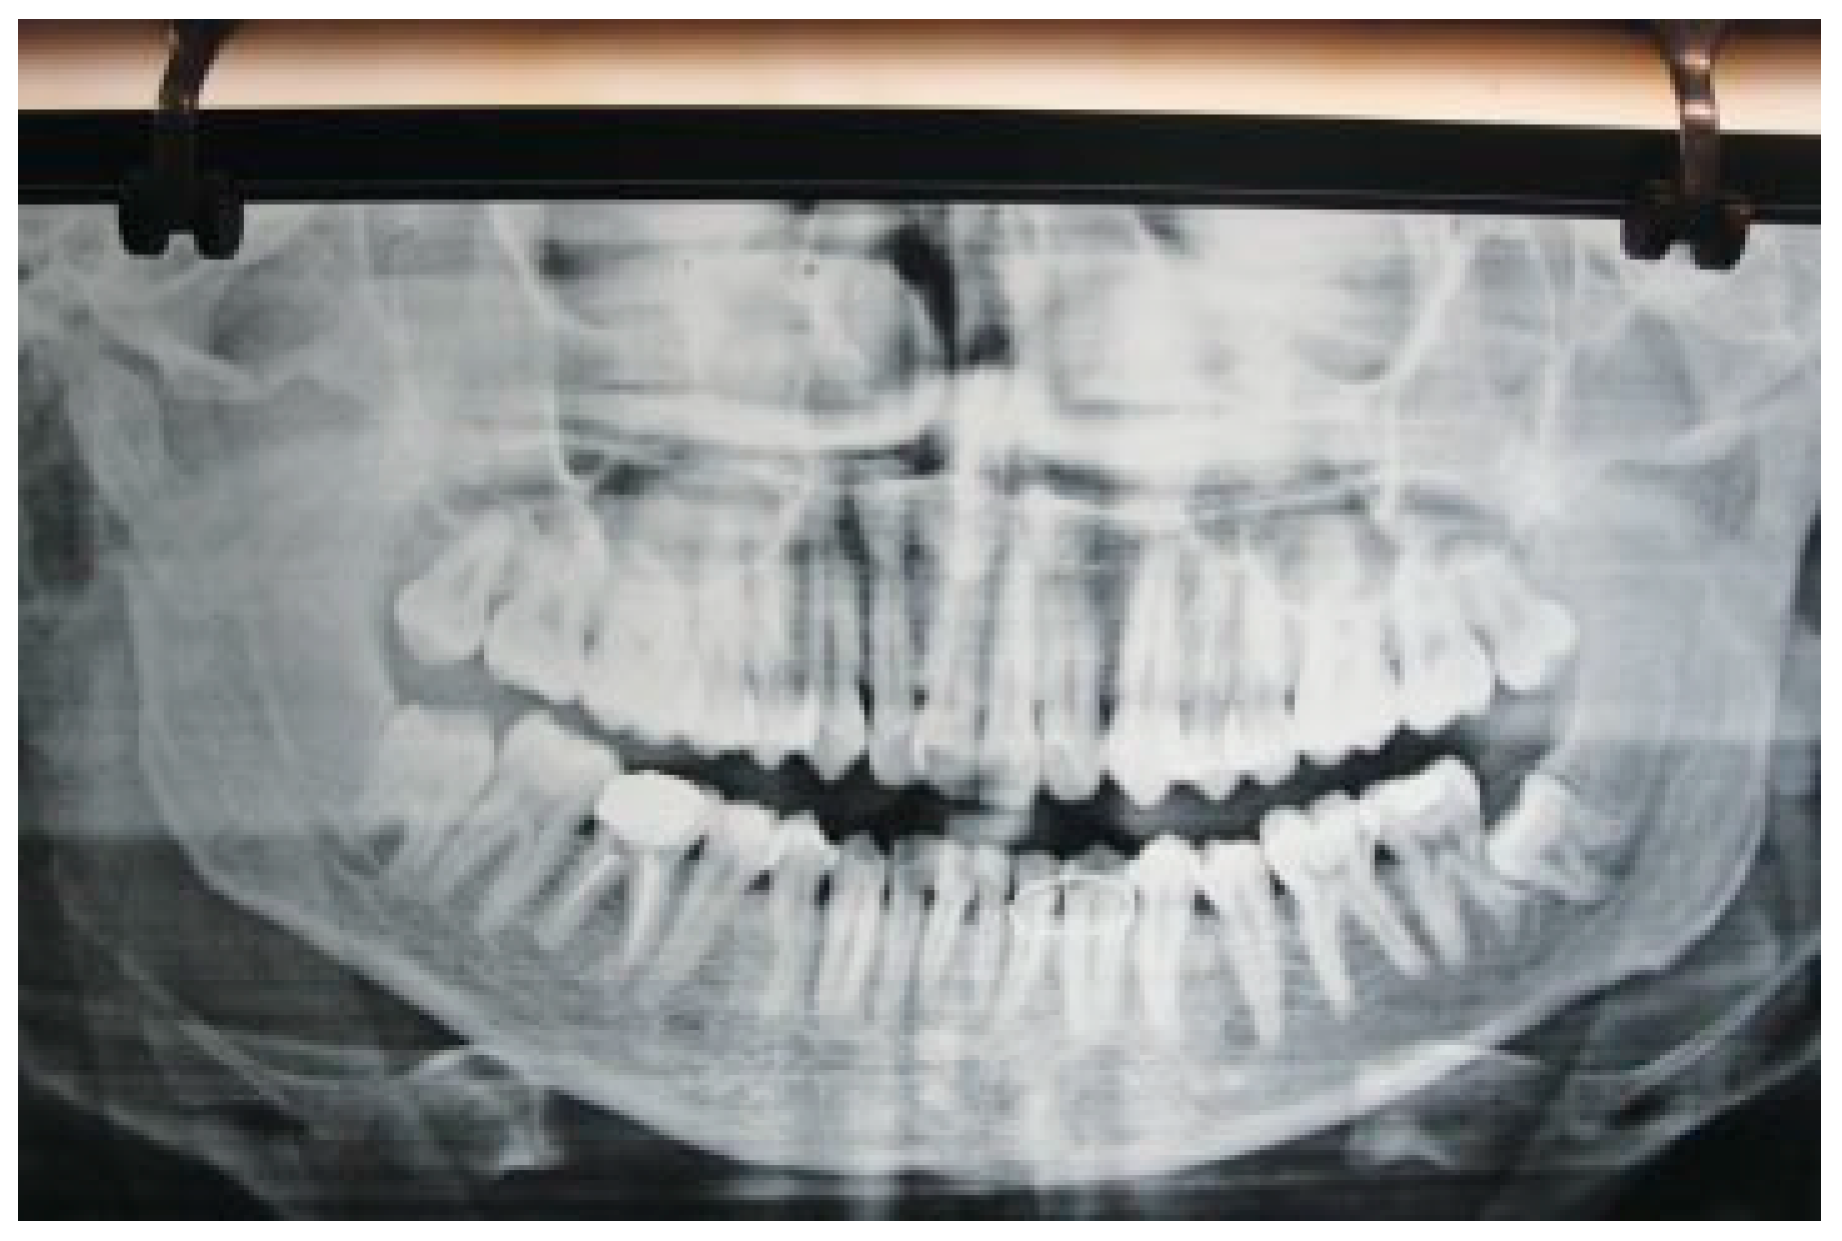

Figure 1. Minimally displaced fractures in panoramic radiograph.

Twenty cases of jaw fracture (14 men and 6 women, age range 19 to 36 years) were selected, and the MMF was done. All patients were treated via closed reduction at our institution between May 2010 and November 2010. Of the 20 cases, 7 were mandibular body fractures, 5 were condylar process and mandibular body fractures, and 8 were mandibular angle fractures. The fractures were all minimally displaced (Figure 1), and manual reduction could be performed in all cases. All patients gave informed consent regarding participation in the study.